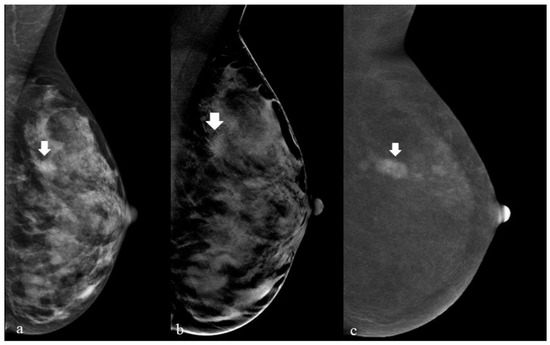

| Histological Results | Visibility | |||||||||

|---|---|---|---|---|---|---|---|---|---|---|

| DM 1 | DM + DBT 2 | Recombined (CEM) 3 | Low Energy (CEM) | Recombined + Low Energy | ||||||

| No | Yes | No | Yes | No | Yes | No | Yes | No | Yes | |

| B2 (N = 30) | 7 | 23 | 0 | 30 | 25 | 5 | 8 | 22 | 6 | 24 |

| B3 (N = 9) | 2 | 7 | 0 | 9 | 6 | 3 | 2 | 7 | 2 | 7 |

| B5a (N = 7) | 1 | 6 | 0 | 7 | 2 | 5 | 1 | 6 | 0 | 7 |

| B5b (N = 3) | 1 | 2 | 0 | 3 | 0 | 3 | 2 | 1 | 0 | 3 |

| Total | 11 | 38 | 0 | 49 | 33 | 16 | 13 | 36 | 8 | 41 |